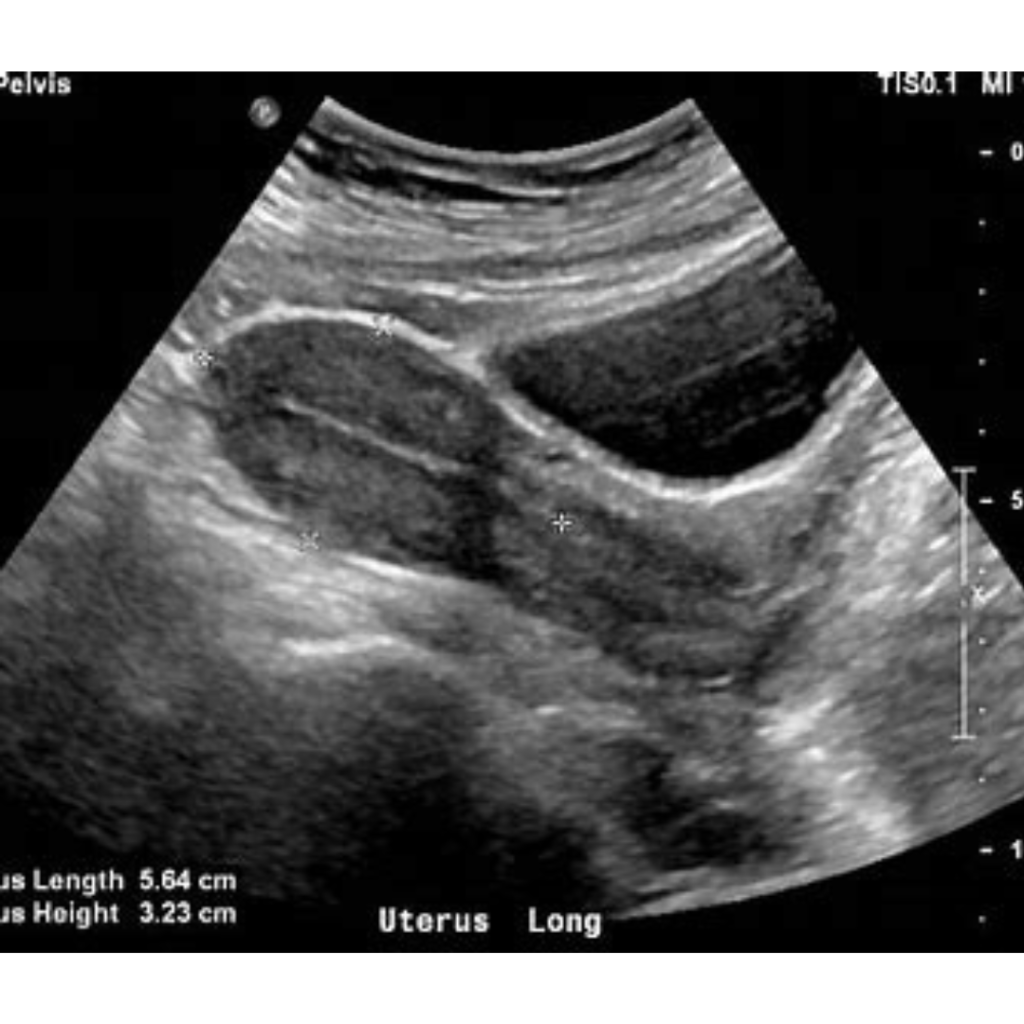

A pelvic ultrasound is a medical test that uses sound waves to create images of the organs in the pelvic area, such as the uterus and ovaries in women, and the bladder and prostate in men. This procedure helps detect cysts, fibroids, tumors, kidney stones, and other abnormalities. Doctors recommend it to investigate symptoms like pelvic pain, abnormal bleeding, or fertility issues. The pelvic ultrasound is a safe, non-invasive tool that provides valuable information for diagnosing and treating various conditions.